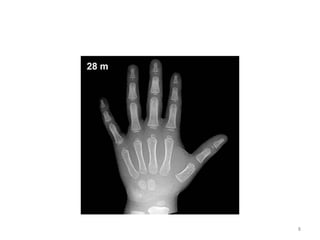

BONE (hand) OSSIFICATION CENTRE APPEARANC E CONJOINT EPIPHYSIS FUSION/U NION First Metacarpal 2-3- 15-17 Proximal phalanges 1.5-2 - 15-18 Metacarpals 2-3 - 15-19 Middle phalanges 2-4 - 15-18 Distal phalanges 2-4 - 15-18 25